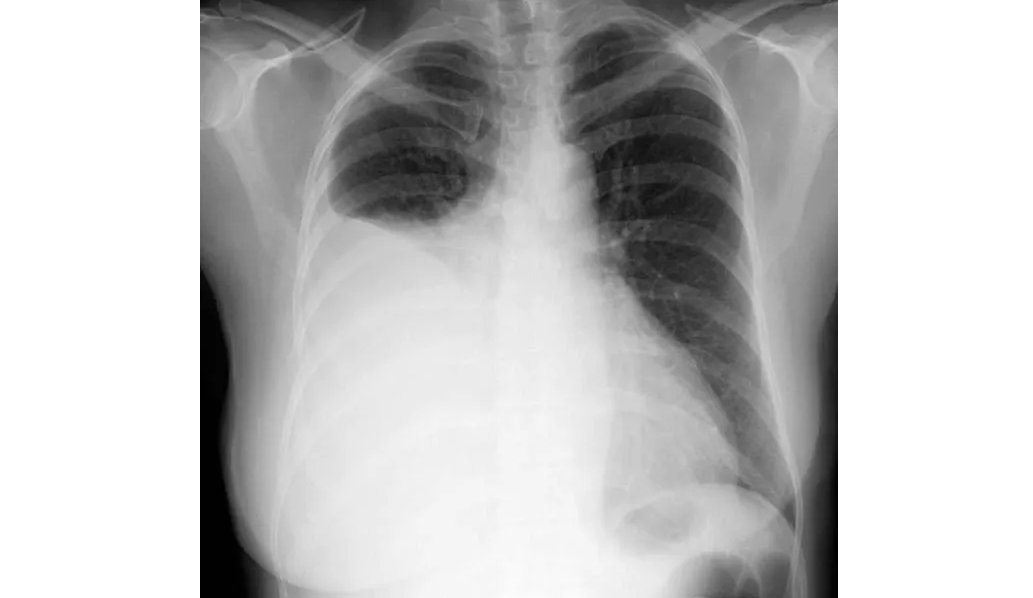

Uso de corticosteroides inhalados y riesgo de internación por neumonía en niños con asma

10 enero 2024